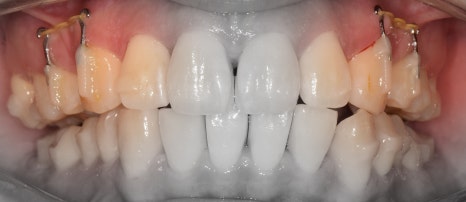

그러면서, 대략 2년이라는 시간이 흘러서

가지런한 치열이 탄생이 되었습니다.

앞서, 1치대 1치 관계에 있던 교합관계들이

1치대 2치의 관계로 바뀐것을 볼 수 있으면서

길쭉하게 느껴졌던, U shape 형태의 악궁이

딱 보기 좋은, U shape 로 바뀌었죠.

이 분은, 코는 높고 예쁘셨기 때문에

조금 더 세련 된 얼굴형을 갖게 되셨습니다.